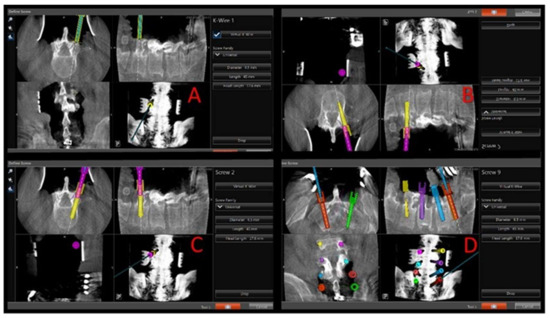

Figure 2. Intraoperative views of navigation screen showing steps of virtual screw placement. (A) Navigated Stryker drill with 3 mm match stick drill bit at anatomical entry point with screen projection showing a 6.5 × 50 mm virtual screw. (B) Navigated Stryker Driver with 5.5 tap accessing the vertebral body through the pedicle with screen projection again showing 6.5 × 50 screw. (C) Navigated Stryker driver with 6.5 × 50 screw with screen projection showing the same 6.5 × 50 virtual screw. The instruments used at each step are color-coded to avoid confusion on the navigation monitor while advancing into the pedicle and vertebral body (match stick drill bit in “A”, green. Tap in “B”, yellow. Screw in “C”, pink. (D) Screen shot showing final screw placement before intra-operative CT done to confirm placement.

Once accuracy is verified, the navigated Stryker electric drill with 3-mm matchstick drill bit is used to make an entry hole into the proximal 1/2 of the pedicle at the appropriate angles given by the navigation system. The Stryker navigation system is calibrated such that the matchstick drill bit projects onto the navigation screen at the desired screw diameter and length (see Figure 2). The appropriate length and diameter of the screw was selected by visualizing virtual screw projection on the Stryker workstation using intraoperative imaging. The pedicle feeler is then used to confirm access into the pedicle. The navigated Stryker Instruments Cordless Driver 3 is then brought into the file and tested for accuracy. There should be an exact match for the hole made by the Stryker electric drill. If there is not an exact match, the system needs to be checked again as described above. The navigated Stryker Cordless Driver 3 with appropriate tap (see Figure 1) is then used to access the vertebral body. The powered taps were manufactured by Stryker specifically for the senior author. Again, the tap bit projects onto the navigation screen at the desired screw diameter and length (see Figure 2). This technique helps assure that a breach will not occur when the actual screw is inserted. The pedicle feeler is again used to check for a breach after the tap is removed.

The novelty of this technique is a combination of using a power driver with virtual screw technology. The visualization approach comes from the initial utilization of only a 3-mm tip and the screen projection of a real-size virtual screw. Using a small 3-mm tip prevents complications and potentially harmful entry into unnecessary neuroanatomy. Visualizing a full-size 6.5 × 50 screw on the screen projection prior to insertion of the PS allows the authors’ to ensure that the screw will avoid hitting any delicate surrounding anatomy. Essentially, the real-size virtual screw visualization and utilization of a small 3-mm match stick tip allow for minimal complications and certainty of the PS trajectory. A pedicle feeler is used to assess the integrity of the tract and confirm system accuracy. The next step uses an appropriate tap on the navigated power driver to access the vertebral body and finally to place and appropriate PS also using the navigated power driver.